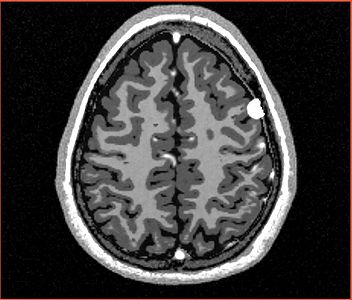

NOTE: red outlines the boundary of the label corresponding to the initial tumor seed!

Seed 1 (default seed from Marcel)

All the following experiments are based on the "thin dura" input labels, and the tumor seed image shown on the right. The tumor label is shown in green color. Note that the tumor is touching the gray matter label.

The seed image can be downloaded File:Seed3.nrrd

The following screenshots capture the same axial slice (#119) of the following images in order: (1) image containing the tumor probabilities, and (2) the simulated Gad enhanced image, both overlayed with the warped tumor/brain tissues labels.